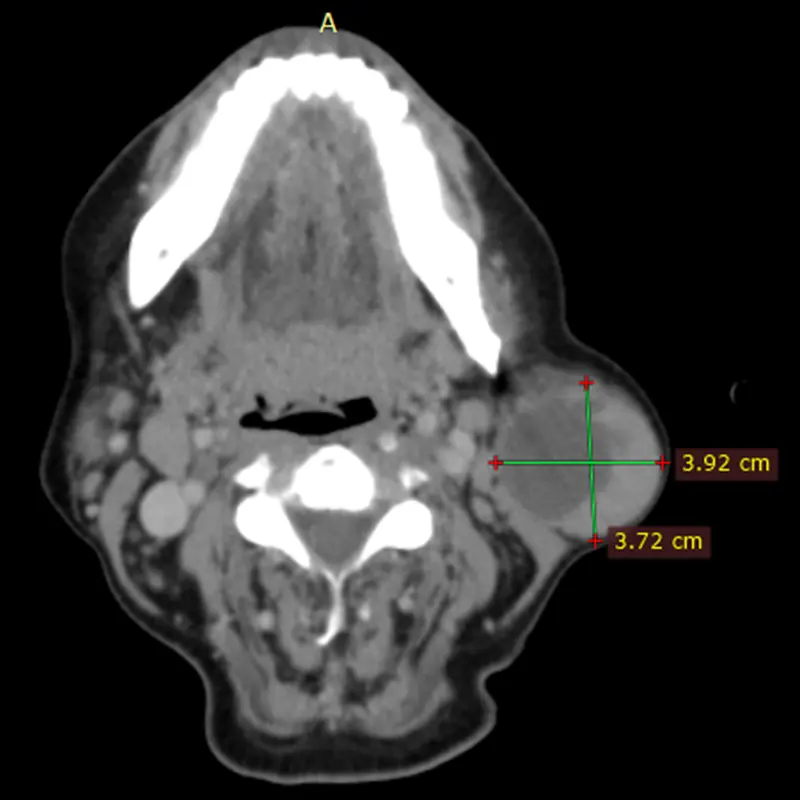

Hiperplasias o hipoplasias condilares

Es una enfermedad rara que se considera un crecimiento patológico y progresivo de uno o ambos cóndilos mandibulares, cuanto más grave es la patología, mayor asimetría y maloclusión desarrolla, que no solo afecta al desarrollo, masticación, deglución, habla, etc. si no que además esta particular entidad afecta altamente al individuo en un nivel psicosocial.